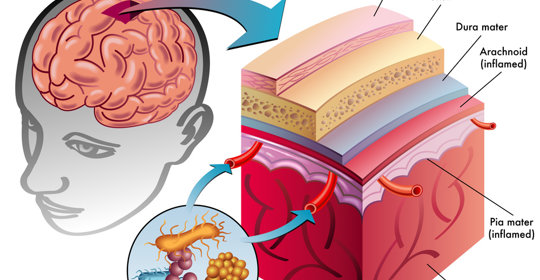

中樞神經系統感染:症狀、後遺症與診療

中樞神經系統感染:型別、傳染與治療

中樞神經系統感染:治療與預後